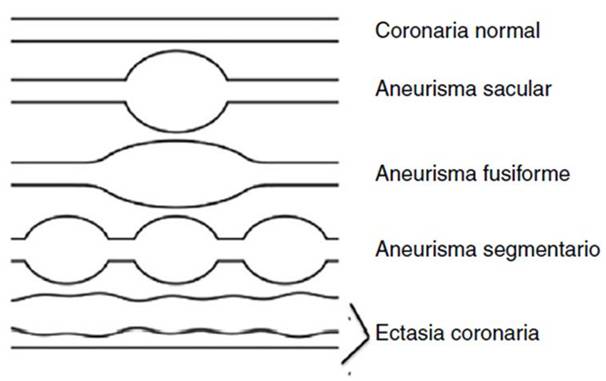

Las manifestaciones cardiacas más frecuentes en los pacientes con EK son las lesiones en arterias coronarias. Actualmente, las lesiones descritas en las arterias de estos pacientes son como ectasias o aneurismas23 (fig. 3). Estas lesiones coronarias se presentan en el 15-25% de todos los

Figura 3 Esquemas de las alteraciones coronarias en la enfermedad de Kawasaki. Modificado de Yim et al.19.